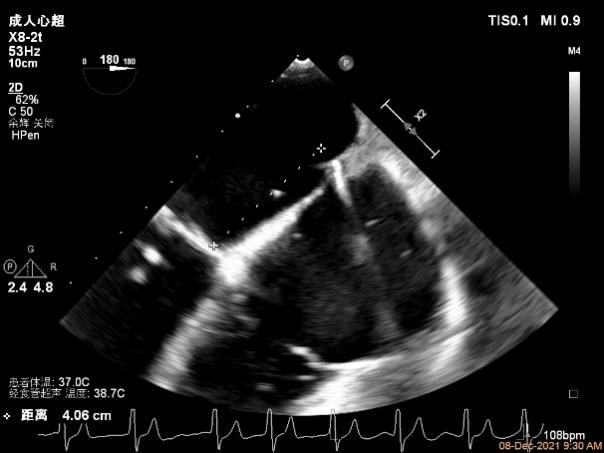

3D视图菲薄的卵圆窝,穿刺点位近似于3点位

3D视图下大鞘位置及长度测量